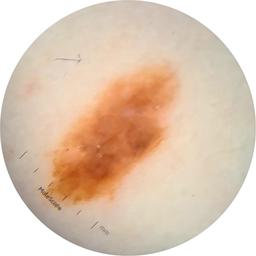

ISIC_9966288

811 x 811

Clinical

Field Value

acquisition_day 475

age_approx 50

anatom_site_1 Trunk

anatom_site_2 Posterior trunk

anatom_site_general posterior torso

concomitant_biopsy False

diagnosis_1 Benign

diagnosis_confirm_type single image expert consensus

family_hx_mm True

image_manipulation instrument only

image_type dermoscopic

lesion_id IL_7153617

patient_id IP_5835518

personal_hx_mm True

sex female